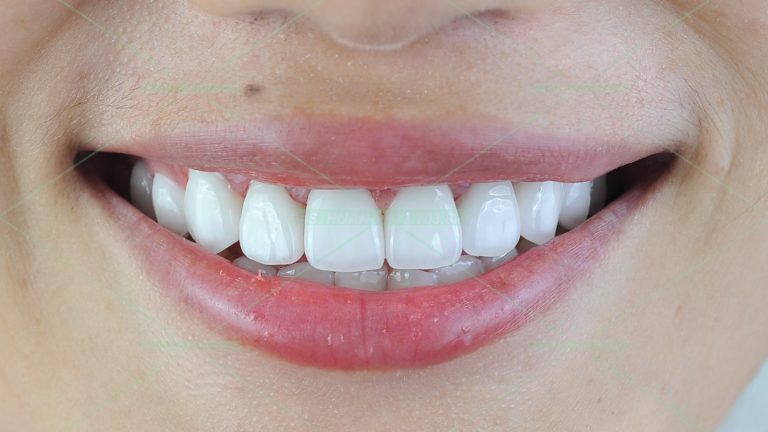

Răng sứ thẩm mỹ – N.T.L

Bạn nữ 29 tuổi làm chủ 1 nhãn hàng thời trang và thường xuyên phải thuyết trình giới thiệu sản phẩm, vì vậy ngoại hình rất quan trọng với bạn, nhất là nụ cười. Đây cũng là 1 ca được tư vấn chỉnh nha trước rồi làm răng sứ, cũng như những nguy cơ khi […]